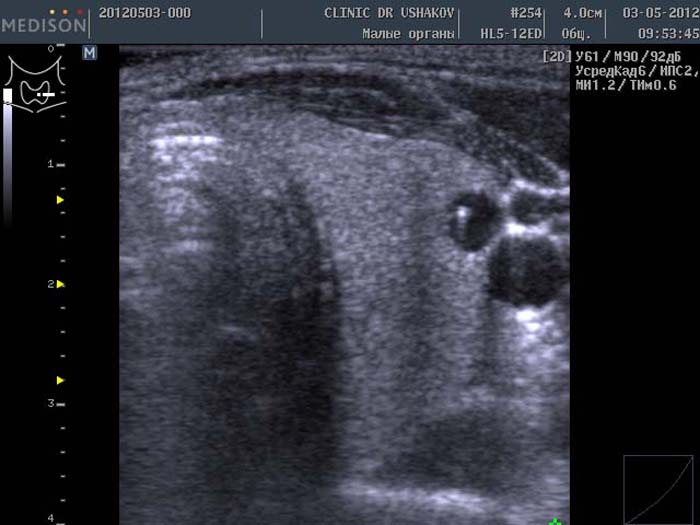

Основным методом диагностики состояний и новообразований щитовидной железы остается УЗИ, которое можно проводить пациентам любого возраста. Это обследование позволяет определить размер, структуру и тип новообразования.

Узлы размером до 1 см обычно выявляются на УЗИ и не требуют дальнейшего обследования, если не наблюдается их рост. Небольшие узлы могут появляться и уменьшаться самостоятельно. Если узел превышает 10 мм, проводится тонкоигольная биопсия для его диагностики.

Для биопсии под контролем УЗИ в полость образования вводится тонкая игла, через которую откачивается небольшое количество содержимого. Жидкость отправляется на цитологическое или гистологическое исследование.